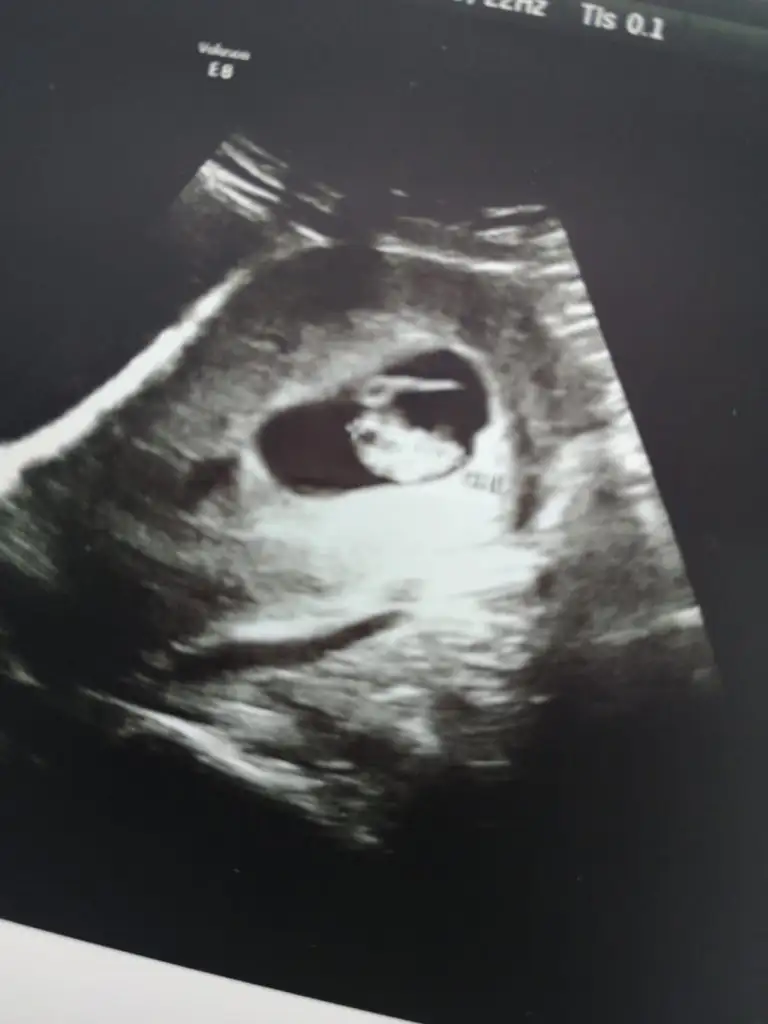

Ultrason görüntüsü 8 haftalık kızlar kimileri cinsiyet yorumu yapıyor anlayan var mı

Eklentiler

• IMG-20220628-WA0001.webp

14,9 KB · Görüntüleme: 110